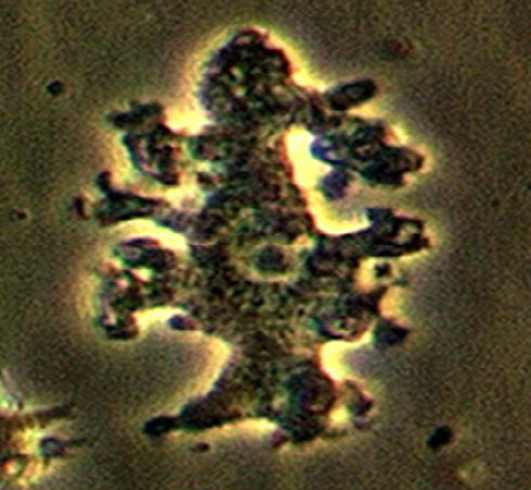

Identify the parasitic stage.

Mention two morphological characteristics of this stage.

Mention the possible human samples used for diagnosis, and the culture medium used.

Mention the diagnostic methods used for ocular infection caused by this parasite.

Acanthamoeba castellanii cyst.

About 15–20 µm in size.

Has a polygonal double wall with many pores.

Samples: CSF, brain tissue, corneal tissue, and skin biopsy.

Culture medium: Non-nutrient agar (1.5%) enriched with Escherichia coli.

Corneal scrapings or sections examined by direct microscopy and staining, or by cultivation.

Laser confocal microscopy can visualize both trophozoites and cysts.